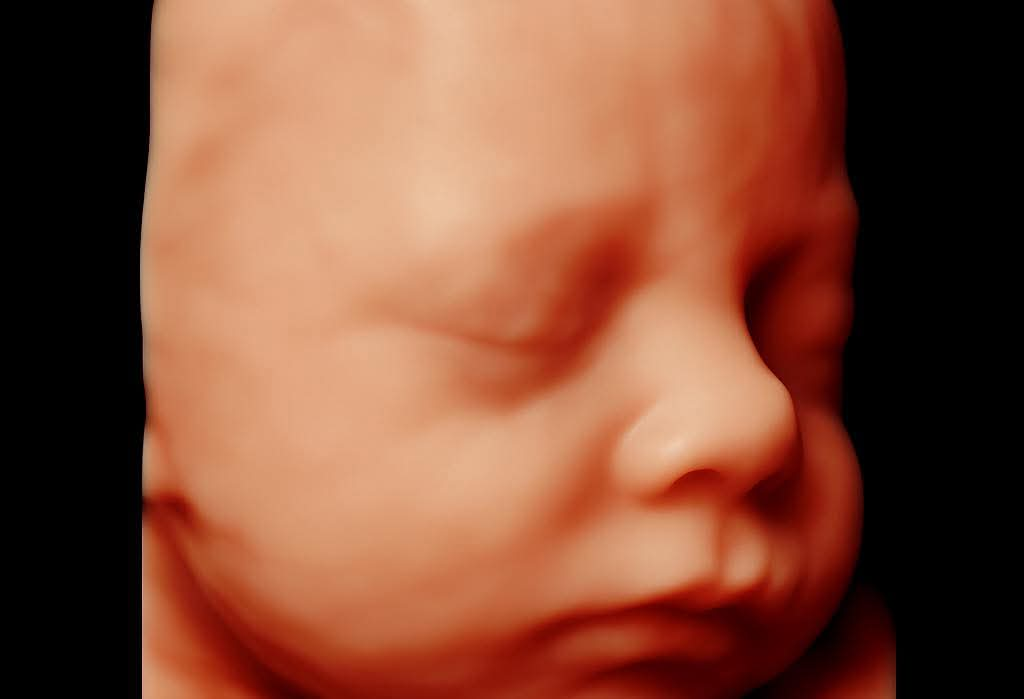

An anomaly scan, also known as a TIFFA scan (Targeted Imaging for Fetal Anomalies), is one of the most important pregnancy scans performed during the second trimester. It is often referred to as the 20-week ultrasound or Level II scan. This scan is usually done between 18 to 22 weeks of pregnancy but can be performed up to 28 weeks of gestational age. The sonographer examines the baby’s anatomy, observing the internal organs and identifying any structural defects or soft markers from head to toe. The scan can detect major congenital deformities such as Down Syndrome (50%), Cleft Lip (75%), Anencephaly, Gastroschisis (98%), Edwards Syndrome (Trisomy 18) (95%), and congenital heart disease (50%).

Yes, there are some limitations. While most anomalies can be identified, the scan is not 100% accurate. Some defects may develop later in pregnancy and cannot be detected during the 18–20-week window. Factors such as obesity, the baby’s position, or multiple pregnancies (twins/triplets) may make it difficult to visualise certain anomalies. Conditions like soft tissue fusion, absence of anal or auditory openings, or cleft palate (beyond the lip) may not be detected.

An anomaly scan at 18–20 weeks cannot guarantee a completely healthy baby at 40 weeks, as many developments occur later. However, in most cases, major anomalies are detected during this scan when performed by experienced professionals using advanced ultrasound machines.

Note: Even if your scan is normal, there remains a small chance of undetected issues. Some heart defects (like coarctation of the aorta, VSDs, ASDs) and conditions such as biliary atresia, bowel obstructions, CDH, or ear/orbital anomalies may appear later in pregnancy. Still, most babies are born healthy and normal after a clear anomaly scan.